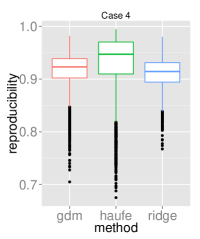

To assess the discriminative performance and reproducibility of the compared methods under varying confounding scenarios, we used the ADNI dataset. We simulated four distinct training scenarios in increasing potential for confounding effects: Case 1: AD + CN subjects, mean age balanced, Case 2: CN + AD, mean age balanced, Case 3: AD + CN, oldest ADs, youngest CNs, Case 4: CN + AD, oldest ADs, youngest CNs.

All models had their respective parameters () cross-validated in an inner fold before performing out-of-sample prediction on a left out test set consisting of equal numbers of AD and CN subjects with balanced mean age. Furthermore, the inner product of training model parameters was compared between folds to assess the reproducibility of models. Training and testing folds were shuffled 100 times to yield a distribution.

The prediction accuracies and the model reproducibility for the above cases are shown in figure 2. The results demonstrate that while GDM is not a purely discriminative model, its predictions outperformed ridge regression in all four cases. Regarding reproducibility, the Haufe et al. (2014) procedure yielded the most stable models since it yields a purely generative model. However, GDM was more reproducible than ridge regression.